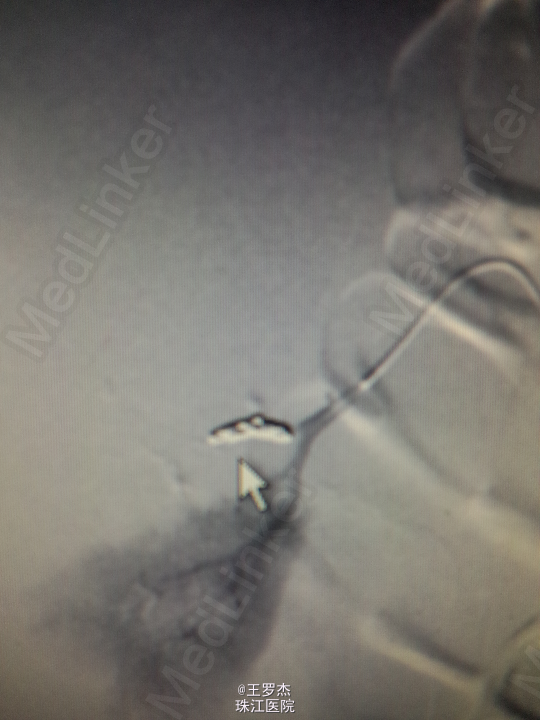

诊断治疗:右肾挫裂伤,保守治疗。3天后复查Hb89g/L,RBC2.65;复查CT提示包膜下及盆腔积血较前增多。请介入科会诊,行右肾动脉选择性栓塞。 介入:右肾挫裂伤,并上极动脉破裂出血及远端多处动静脉瘘形成,成功行超选择性病变血管栓塞术。